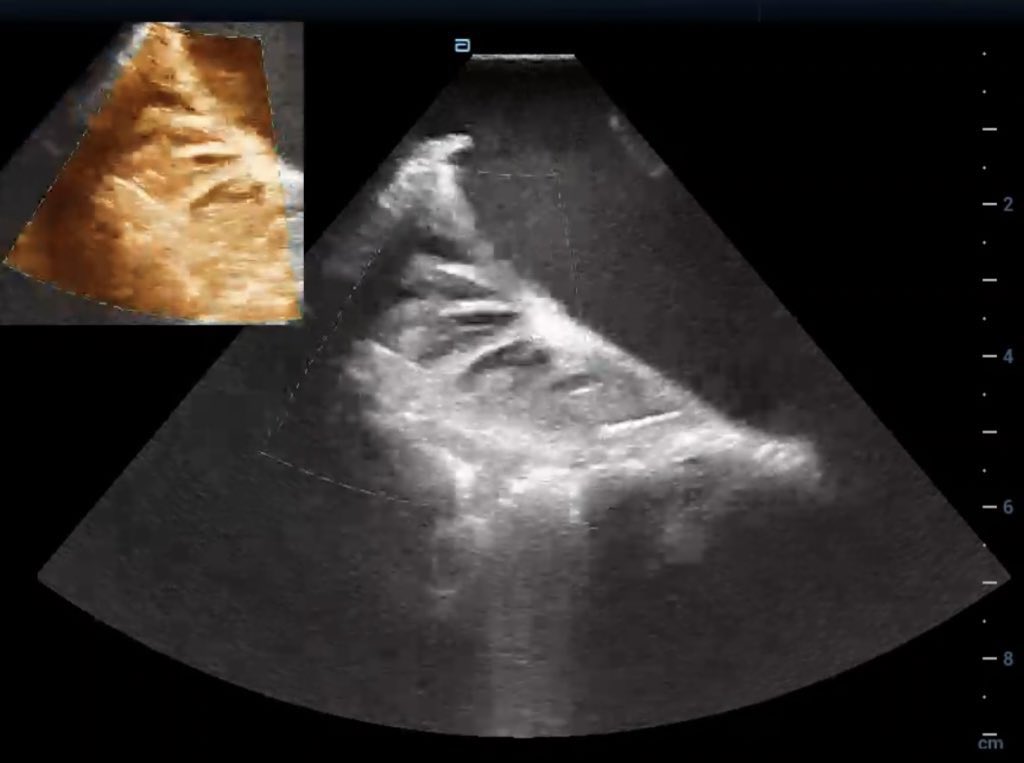

Ventricular tachycardia with predominantly epicardial circuit with entrainment and termination. Endocardial map shows focal breakthrough near the critical epicardial area. Vivek Y. Reddy Jacob Koruth William Whang Jalaj Garg @mohitkturagam @BiosenseWebster #EPeeps #AblateVT